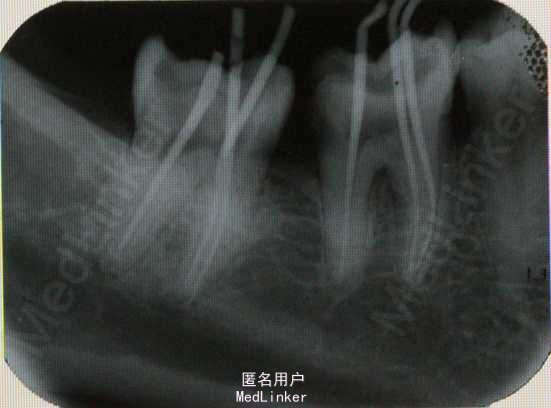

患者,男,48岁。左下后牙疼痛3天。

口内检查:见36,37牙冠大面积龋坏,进髓。扣++,冷+,探+。无明显松动,颊侧无瘘管。牙周状况一般。 牙片示:36,37深龋近髓,37远中根尖有明显暗影。

诊断:36慢性牙髓炎;37慢性根尖周炎。 处理:36,37根管治疗+纤维桩+冠修复

粗大根管常见于上颌前牙、上颌后牙腭根和下颌远中根。若扩挫清理不完善,很容易遗留管壁的感染物。另外,粗大根管可能同时伴随较大根尖孔,这就给根尖的严密充填增加了难度,容易使根尖密封不完全,从而导致症状不缓解或复发。